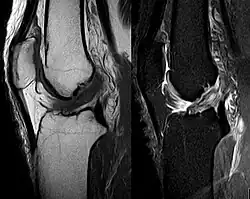

Bildgebende Verfahren

Die Diagnose kann mit bildgebenden Verfahren – namentlich der Magnetresonanztomographie (MRT, „Kernspin“) – bestätigt werden. Dabei ist allerdings zu beachten, dass die Interpretation der MRT in der Diagnostik eines Kreuzbandrisses zu 20 Prozent falsche Diagnosen liefert. Hier kommt es auf die sogenannten Schnittbilder und die geeignete Positionierung des Kniegelenkes bei der MRT-Untersuchung an. Der Radiologe sollte die genaue Vorgeschichte kennen, die zur Verletzung führte, und auch Erfahrung in der Untersuchung eines verletzten Gelenkes haben, um Fehlbeurteilungen zu vermeiden. Im Vergleich zur MRT liegt die Fehlerquote bei dem erheblich einfacher durchzuführenden Lachman-Test bei nur 10 Prozent.[85][86][87][88] Die MRT ist daher in der Regel zur Diagnose eines vorderen Kreuzbandrisses weniger sensitiv und weniger spezifisch als die klinische Befundung durch einen qualifizierten Orthopäden.[89] Das Ergebnis einer MRT hat nur relativ selten einen Einfluss auf die klinische Entscheidungsfindung[90] und sollte keinen Ersatz für eine sorgfältige Anamnese und Palpation darstellen.[15] Mehrere Studien kommen zu dem Schluss, dass eine MRT nur bei komplizierteren unklaren Knieverletzungen – und dabei eher zum Erstellen einer Ausschlussdiagnose[91] – sinnvoll ist.[92][93]

Röntgenaufnahmen leisten keinen unmittelbaren Beitrag zur Diagnosestellung einer Kreuzbandruptur. Beide Kreuzbänder sind – ob gerissen oder nicht – im Röntgenbild nicht sichtbar. Wird dennoch geröntgt, so kann dies der Diagnosestellung von möglichen knöchernen Begleitverletzungen dienen.